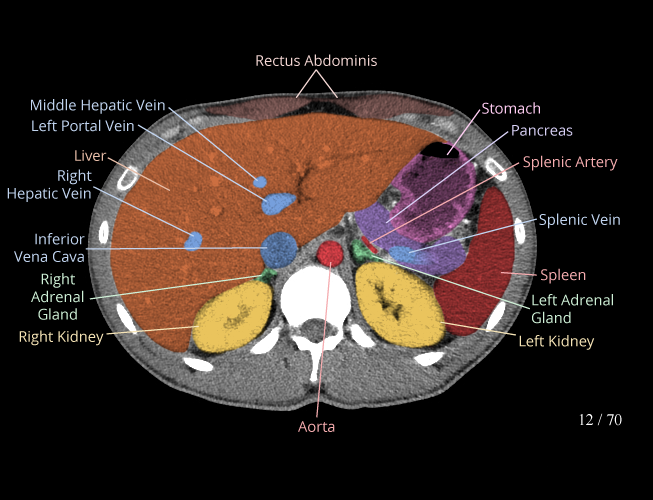

Body

Covers abdominal CT anatomy.